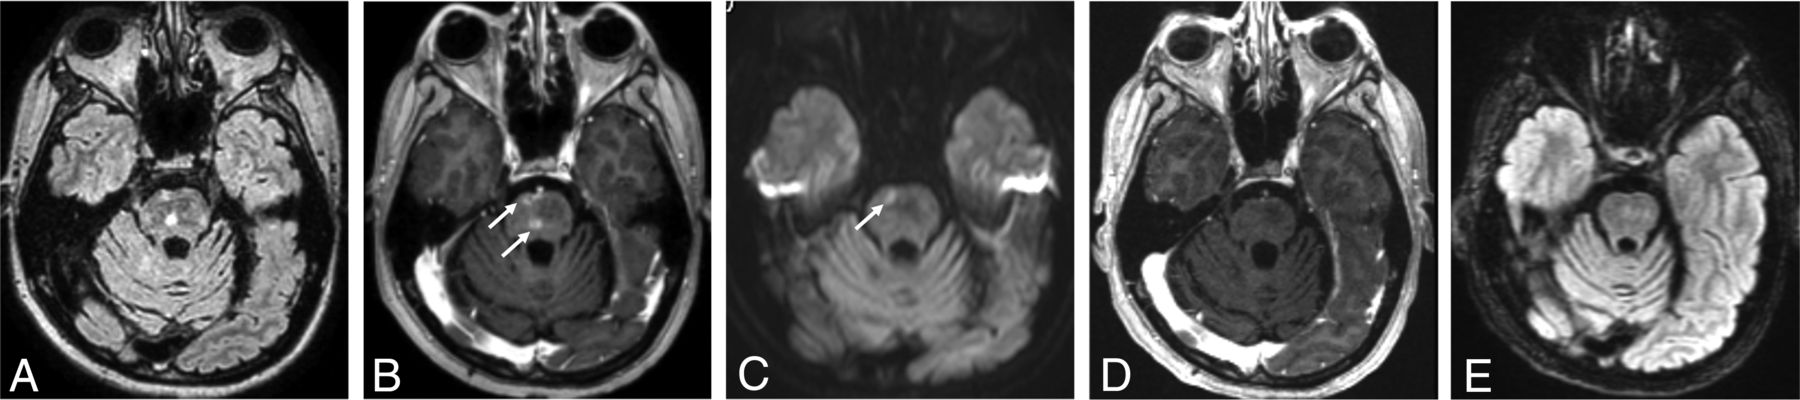

A 37-year-old man diagnosed with PIPG. He had a history of pineoblastoma treated with resection and a posterior fossa meningioma treated by resection and whole-brain irradiation 12 years before, and he presented with migraine-like headache, seizure, right-sided hemiparesis, and aphasia. He was treated with verapamil, aspirin, and valproic acid. He completely recovered from the symptoms. A FLAIR image (A) shows hyperintensity (arrow) with leptomeningeal enhancement in the left temporoparietal region on the axial (B) and sagittal (C) postcontrast T1-weighted images (arrows). Diffusion-weighted imaging (D) and ADC (E) show vasogenic edema (high signal on DWI without low signal on ADC) (arrows).

PIPG was postulated in 2011, with clinical features of absence of acute headache, stroke-like deficits, and MR imaging features of focal cortical or leptomeningeal enhancement overlying an ictal region without adjacent white matter involvement (Fig 5).9 Unlike SMART syndrome, PIPG is observed in all cortical regions, while SMART syndrome occurs with predominance in the temporal, parietal, and occipital lobes. A correlation between steroid introduction and clinical improvement could not be established in patients with PIPG, unlike in patients with SMART syndrome or ALERT syndrome.22

A 60-year-old man with ALERT syndrome. He had a history of atypical meningioma treated with resection and radiation therapy 12 years ago and presented with impaired consciousness, left homonymous hemianopia, and left-sided weakness. He was treated with steroids, but left-sided weakness persisted. The FLAIR (A) image shows hyperintensity with patchy enhancement in the right temporoparietal region on the axial (B) and sagittal (C) postcontrast T1-weighted images (arrows).

ALERT syndrome was established in 2013 and is characterized by clinical features of long-lasting impaired consciousness, seizures, and stroke-like symptoms and by MR imaging features of multifocal patchy enhancement or focal leptomeningeal enhancement associated with T2/FLAIR intensity in the corresponding area (Fig 6).10,22 Steroid efficacy was shown to be evident in patients with ALERT syndrome, with rapid symptom recovery within a few days following steroid introduction.22